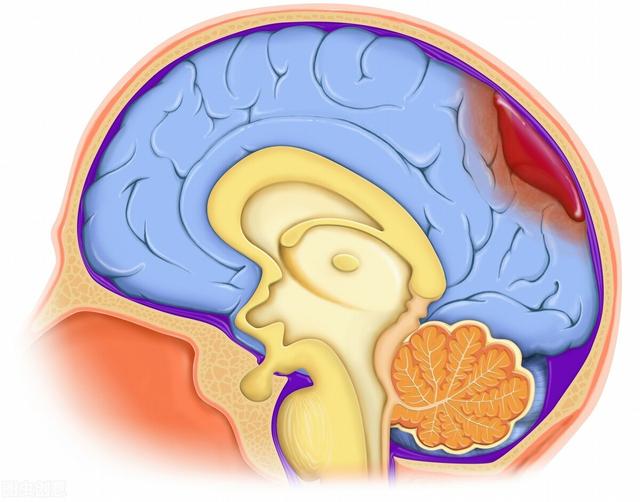

脳出血は一般に脳出血と呼ばれ、脳血管障害の一種であり、中高年の高血圧患者によくみられる重篤な脳合併症である。脳出血は脳実質の血管破裂による非外傷性出血を指し、主な原因は高血圧症、脳動脈硬化症、頭蓋内血管奇形などである。脳出血は発症が早く、救急対応時間が短く、死亡率が高いため、事前に予兆を把握し、応急処置の知識を習得しておく必要がある。

脳出血(脳内出血)とは、一般に脳出血と呼ばれ、脳の血管が非外傷性で破裂し、脳実質に血液が集まることを指す。脳内出血の発症率は10万人当たり12~15人で、脳梗塞に次いで高い。脳出血の発症率は非常に危険であり、発症後30日以内の死亡率は35%~52%と高く、6ヶ月後に自分の命を自分で守れる能力を回復できるのは20%程度である。したがって、脳出血の治療法を知り、事前に予防することが重要である。

脳出血は、一般に脳出血と呼ばれ、一般的でより重篤な急性脳血管障害である。脳出血は一般的で重篤な急性脳血管障害で、毎年季節の変わり目の秋、冬、春に発症し、過労や精神的興奮などが誘因となり、片麻痺、失語症、意識障害などの神経障害をきたすことが多い。脳出血は急速に発症し、高い確率で障害や死亡をもたらす非常に危険な病気です。早期に発見し治療しなければ、重大な結果を招く可能性があります。